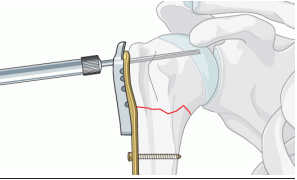

有刷骨钻,骨锯已经不能满足更精细的手术要求。随着医疗水平的发达骨钻骨锯已逐渐升级换代成无刷电机。无刷骨钻骨锯力大、切锯速度快、使用效果更好、安全可靠、效率更高。

主要用于创伤手术中钢板螺钉打孔。骨钻穿孔后上钢板螺钉固定,骨伤内固定。